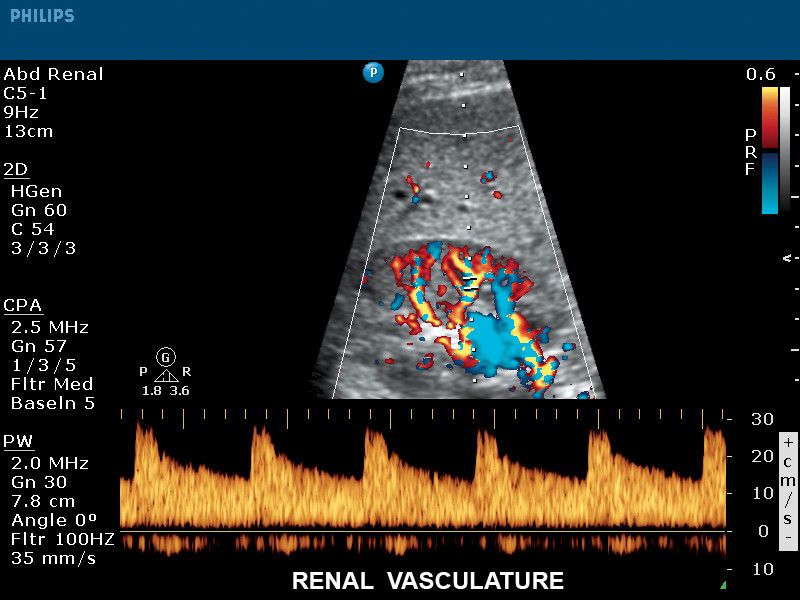

Кровеносные сосуды почек, датчик C5-1